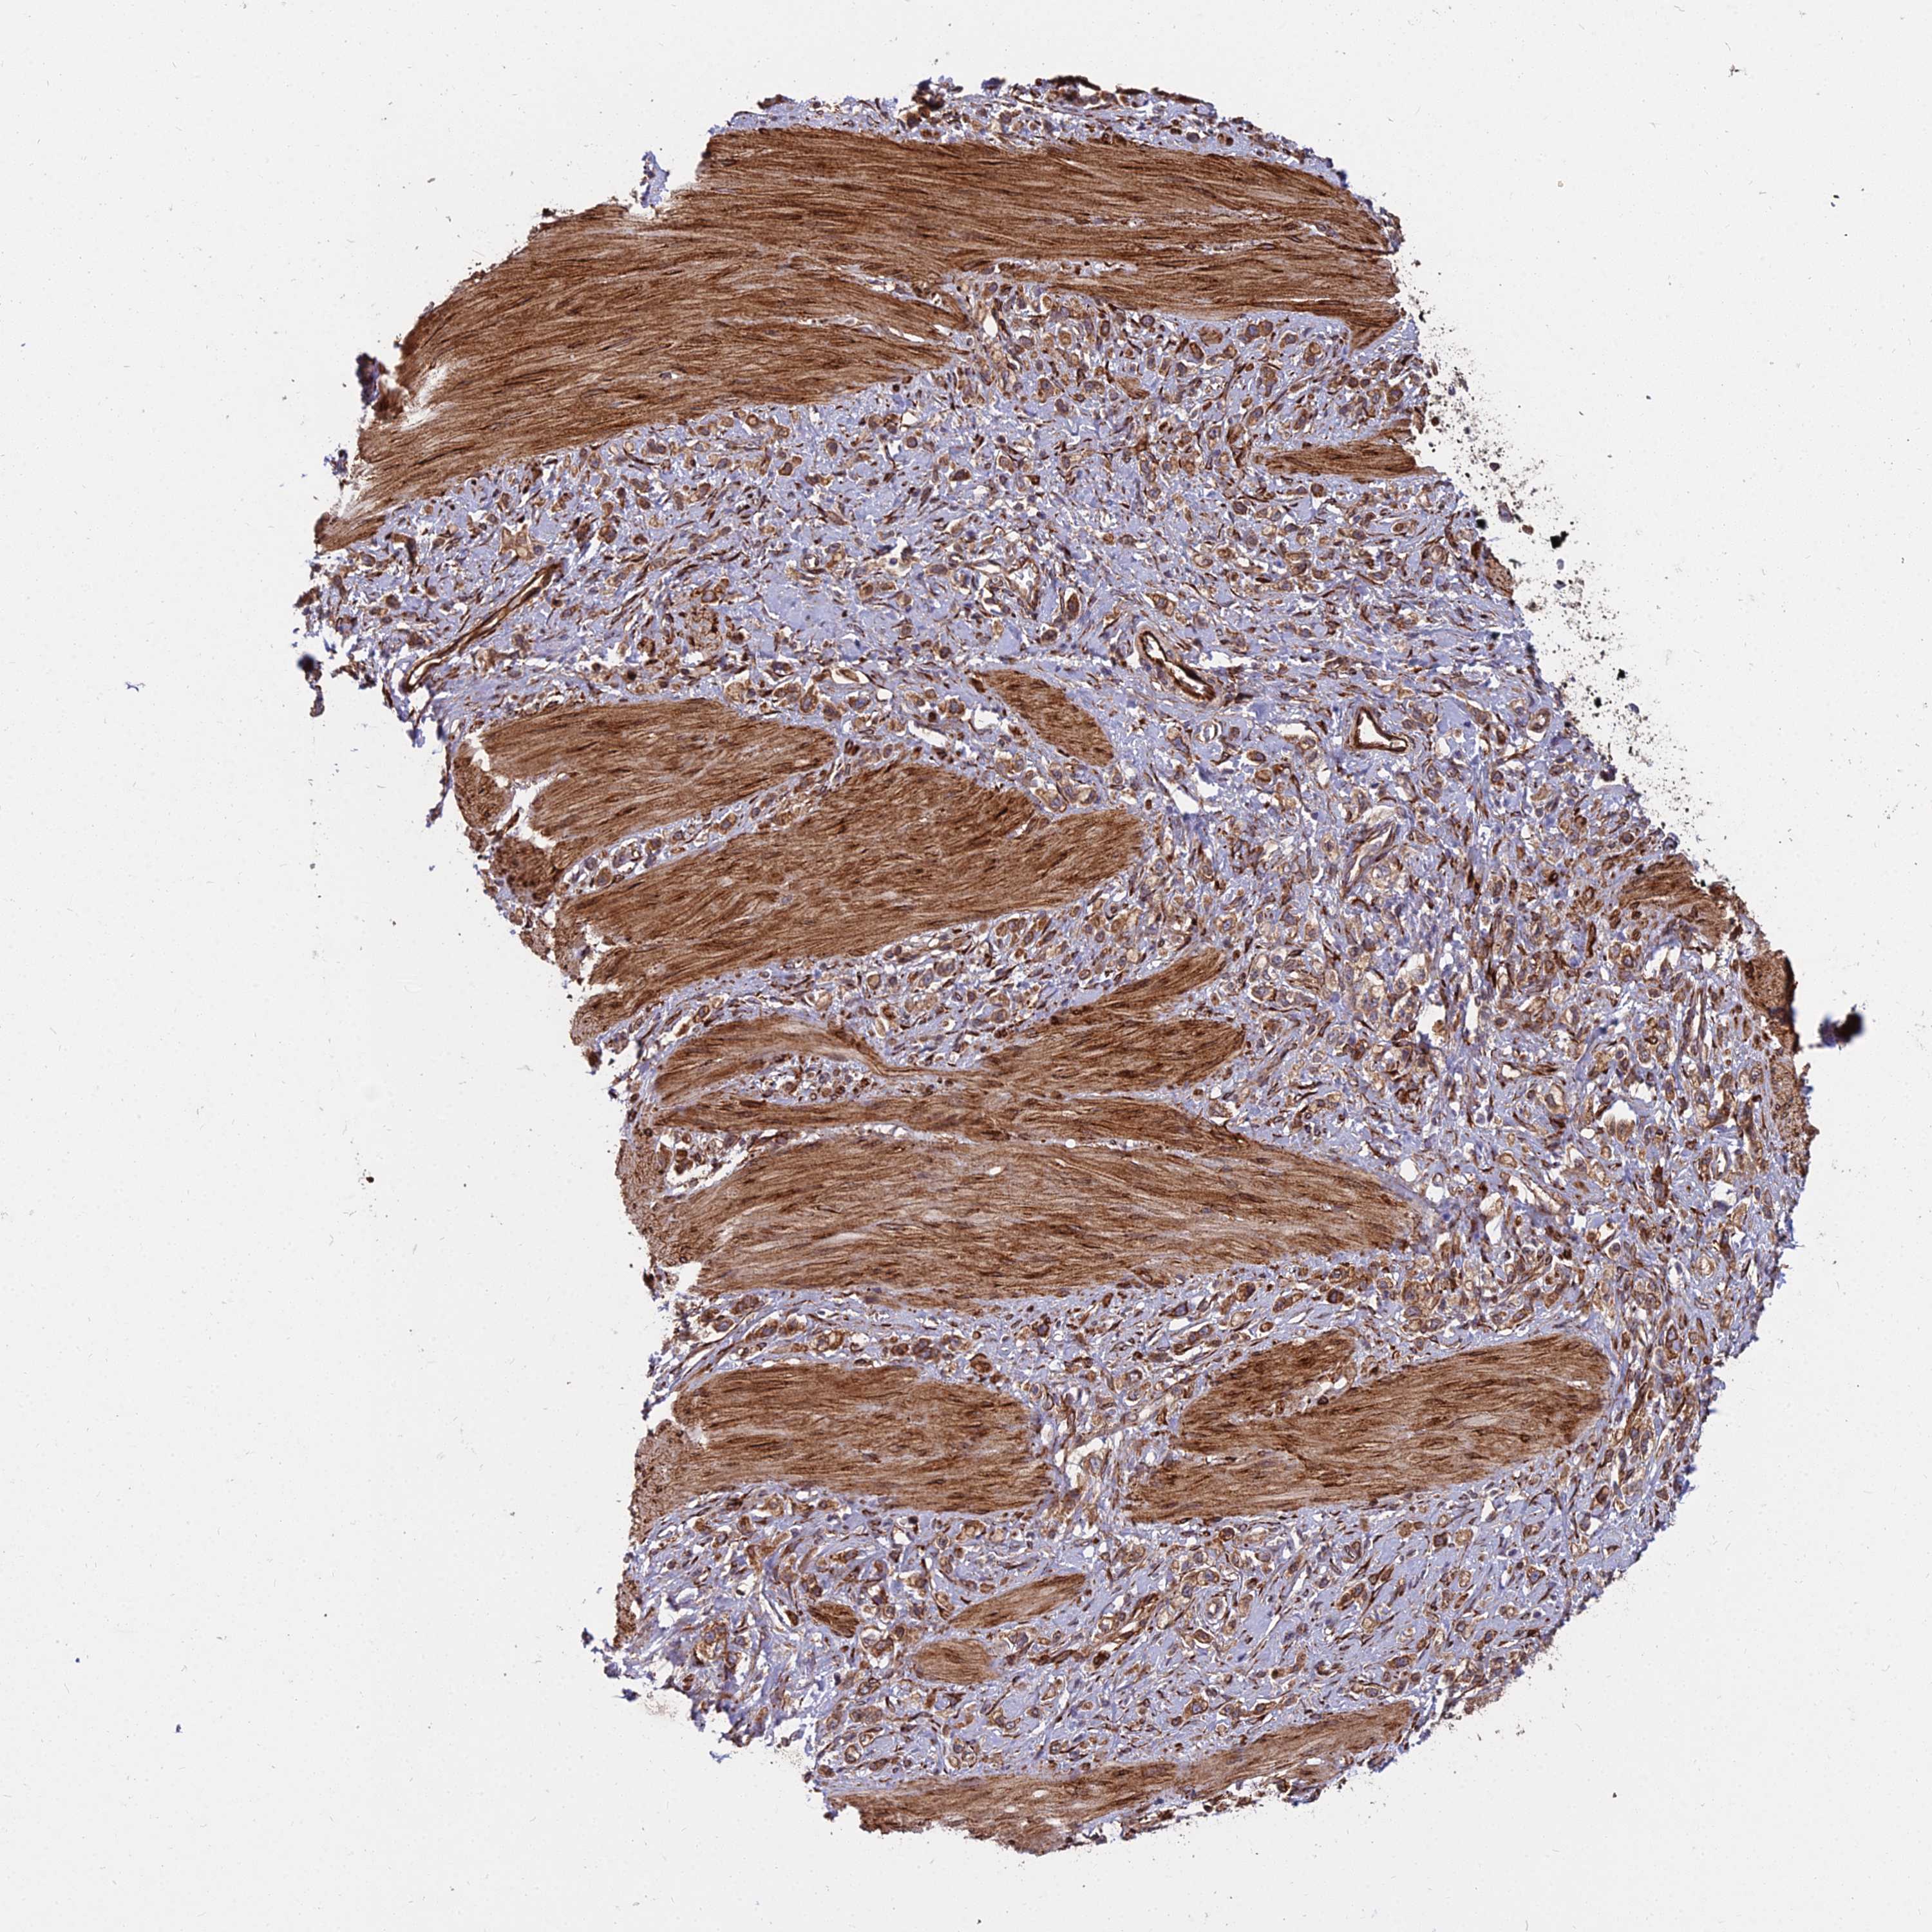

STOMACH CANCER - Protein expressioni

A mouse-over function shows sample information and annotation data. Click on an image to view it in a full screen mode. Samples can be filtered based on level of antibody staining by selecting one or several of the following categories: high, medium, low and not detected. The assay and annotation is described here.

Note that samples used for immunohistochemistry by the Human Protein Atlas do not correspond to samples in the TCGA dataset.

Antibody stainingi

Antibody staining in the annotated cell types in the current human tissue is reported as not detected, low, medium, or high, based on conventional immunohistochemistry profiling in selected tissues. This score is based on the combination of the staining intensity and fraction of stained cells.

Each image is clickable and will lead to virtual microscopy that enables deeper exploration of all samples and also displays staining intensity scores, fraction scores and subcellular localization as well as patient and tissue information for each sample.

Antibody HPA045217

Staining

High

Medium

Low

Not detected

Intensity

Strong

Moderate

Weak

Negative

Quantity

>75%

75%-25%

<25%

None

Location

Nuclear

Cytoplasmic/membranous

Cytoplasmic/membranous,nuclear

Adenocarcinoma, NOS